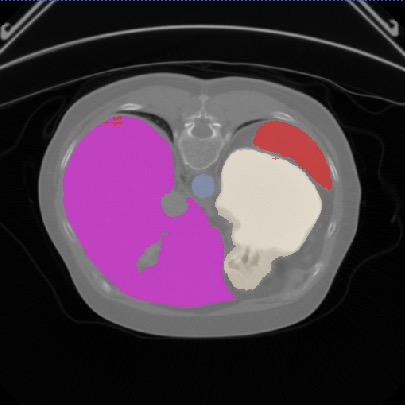

Transformers, the default model of choices in natural language processing, have drawn scant attention from the medical imaging community. Given the ability to exploit long-term dependencies, transformers are promising to help atypical convolutional neural networks (convnets) to overcome its inherent shortcomings of spatial inductive bias. However, most of recently proposed transformer-based segmentation approaches simply treated transformers as assisted modules to help encode global context into convolutional representations without investigating how to optimally combine self-attention (i.e., the core of transformers) with convolution. To address this issue, in this paper, we introduce nnFormer (i.e., Not-aNother transFormer), a powerful segmentation model with an interleaved architecture based on empirical combination of self-attention and convolution. In practice, nnFormer learns volumetric representations from 3D local volumes. Compared to the naive voxel-level self-attention implementation, such volume-based operations help to reduce the computational complexity by approximate 98% and 99.5% on Synapse and ACDC datasets, respectively. In comparison to prior-art network configurations, nnFormer achieves tremendous improvements over previous transformer-based methods on two commonly used datasets Synapse and ACDC. For instance, nnFormer outperforms Swin-UNet by over 7 percents on Synapse. Even when compared to nnUNet, currently the best performing fully-convolutional medical segmentation network, nnFormer still provides slightly better performance on Synapse and ACDC.